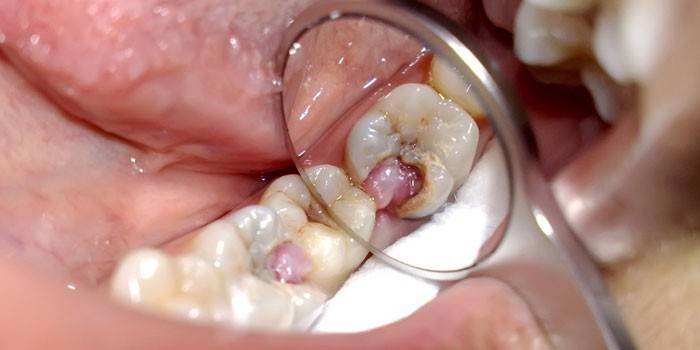

Belirtilen hastalık şekli kendiliğinden gelişir ve hasta aniden ağrımaya başladığından şikayet eder. Akut minber, önce emaye yapı içinde, sonra daha derin, siyah yabancı maddeler içeren kahverengi bir oyuk görünümü ile karakterize edilir. Diş kök kanalları acı çeker, geceleri veya sıcak yemek yerken ağrı şiddetlenir. Enflamatuar sürecin oluşumunun aralarında birkaç nedeni vardır:

Örneğin, bir yanal kesici aletten mağduru kurtarmak için, pulpitisin her çürüme semptomlarına zamanında yanıt verirken ne kadar farklı olduğunu bulmak yararlıdır. İlk durumda, klasik dolgudan vazgeçilebilir ve ikincisinde, önceden tahrip edilen dişin iltihaplı sinirinin çıkarılmasından önce bir çıkarma prosedürü gerekir. Bu sürecin fotoğrafları sağlıklı insanları şok ediyor ve işlem sırasındaki duygular en hoş değil.